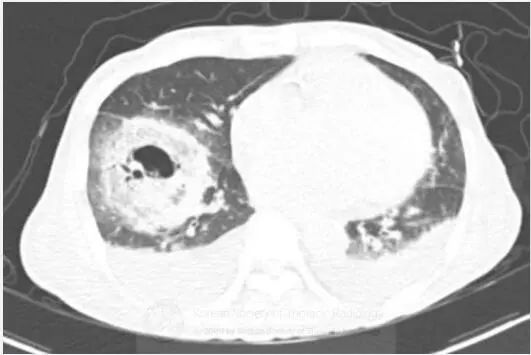

图1胸片示右肺下叶空洞性实变和左肺下叶实变。CT示右肺下叶类圆形实变伴中央磨玻璃影(反晕征),和空洞性病变。可见双侧胸腔积液。

支气管镜活检,真菌菌丝提示毛霉病。

诊断:毛霉病